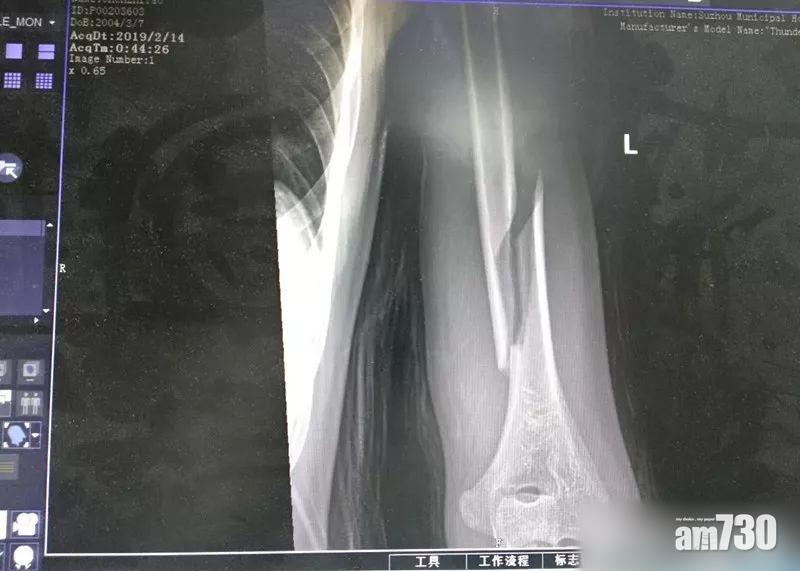

陳父立即將兒子送到醫院,醫生為陳男照X光後,證實其肱骨螺旋性骨折,即骨骼中間受力斷開。醫生更表示,「肱骨是人上肢骨骼中最堅硬的,一般肱骨的骨折,多為橫斷形」,肱骨螺旋性骨折非常罕見,一般多見於工傷意外。陳男接受手術後已無大礙,但因部分神經受損,手部功能未知能否百分百復原。